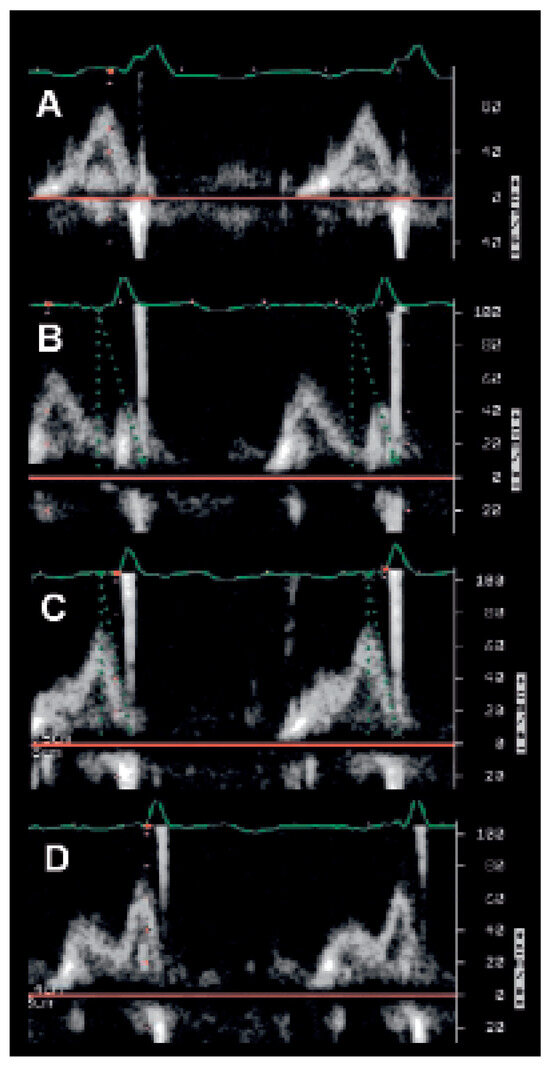

The incidence of heart failure is increasing and patients are threatened to die of pump failure as well as of sudden cardiac death (SCD). Lately, cardiac resynchronisation therapy (CRT) has been introduced to treat patients with persistent heart fail...